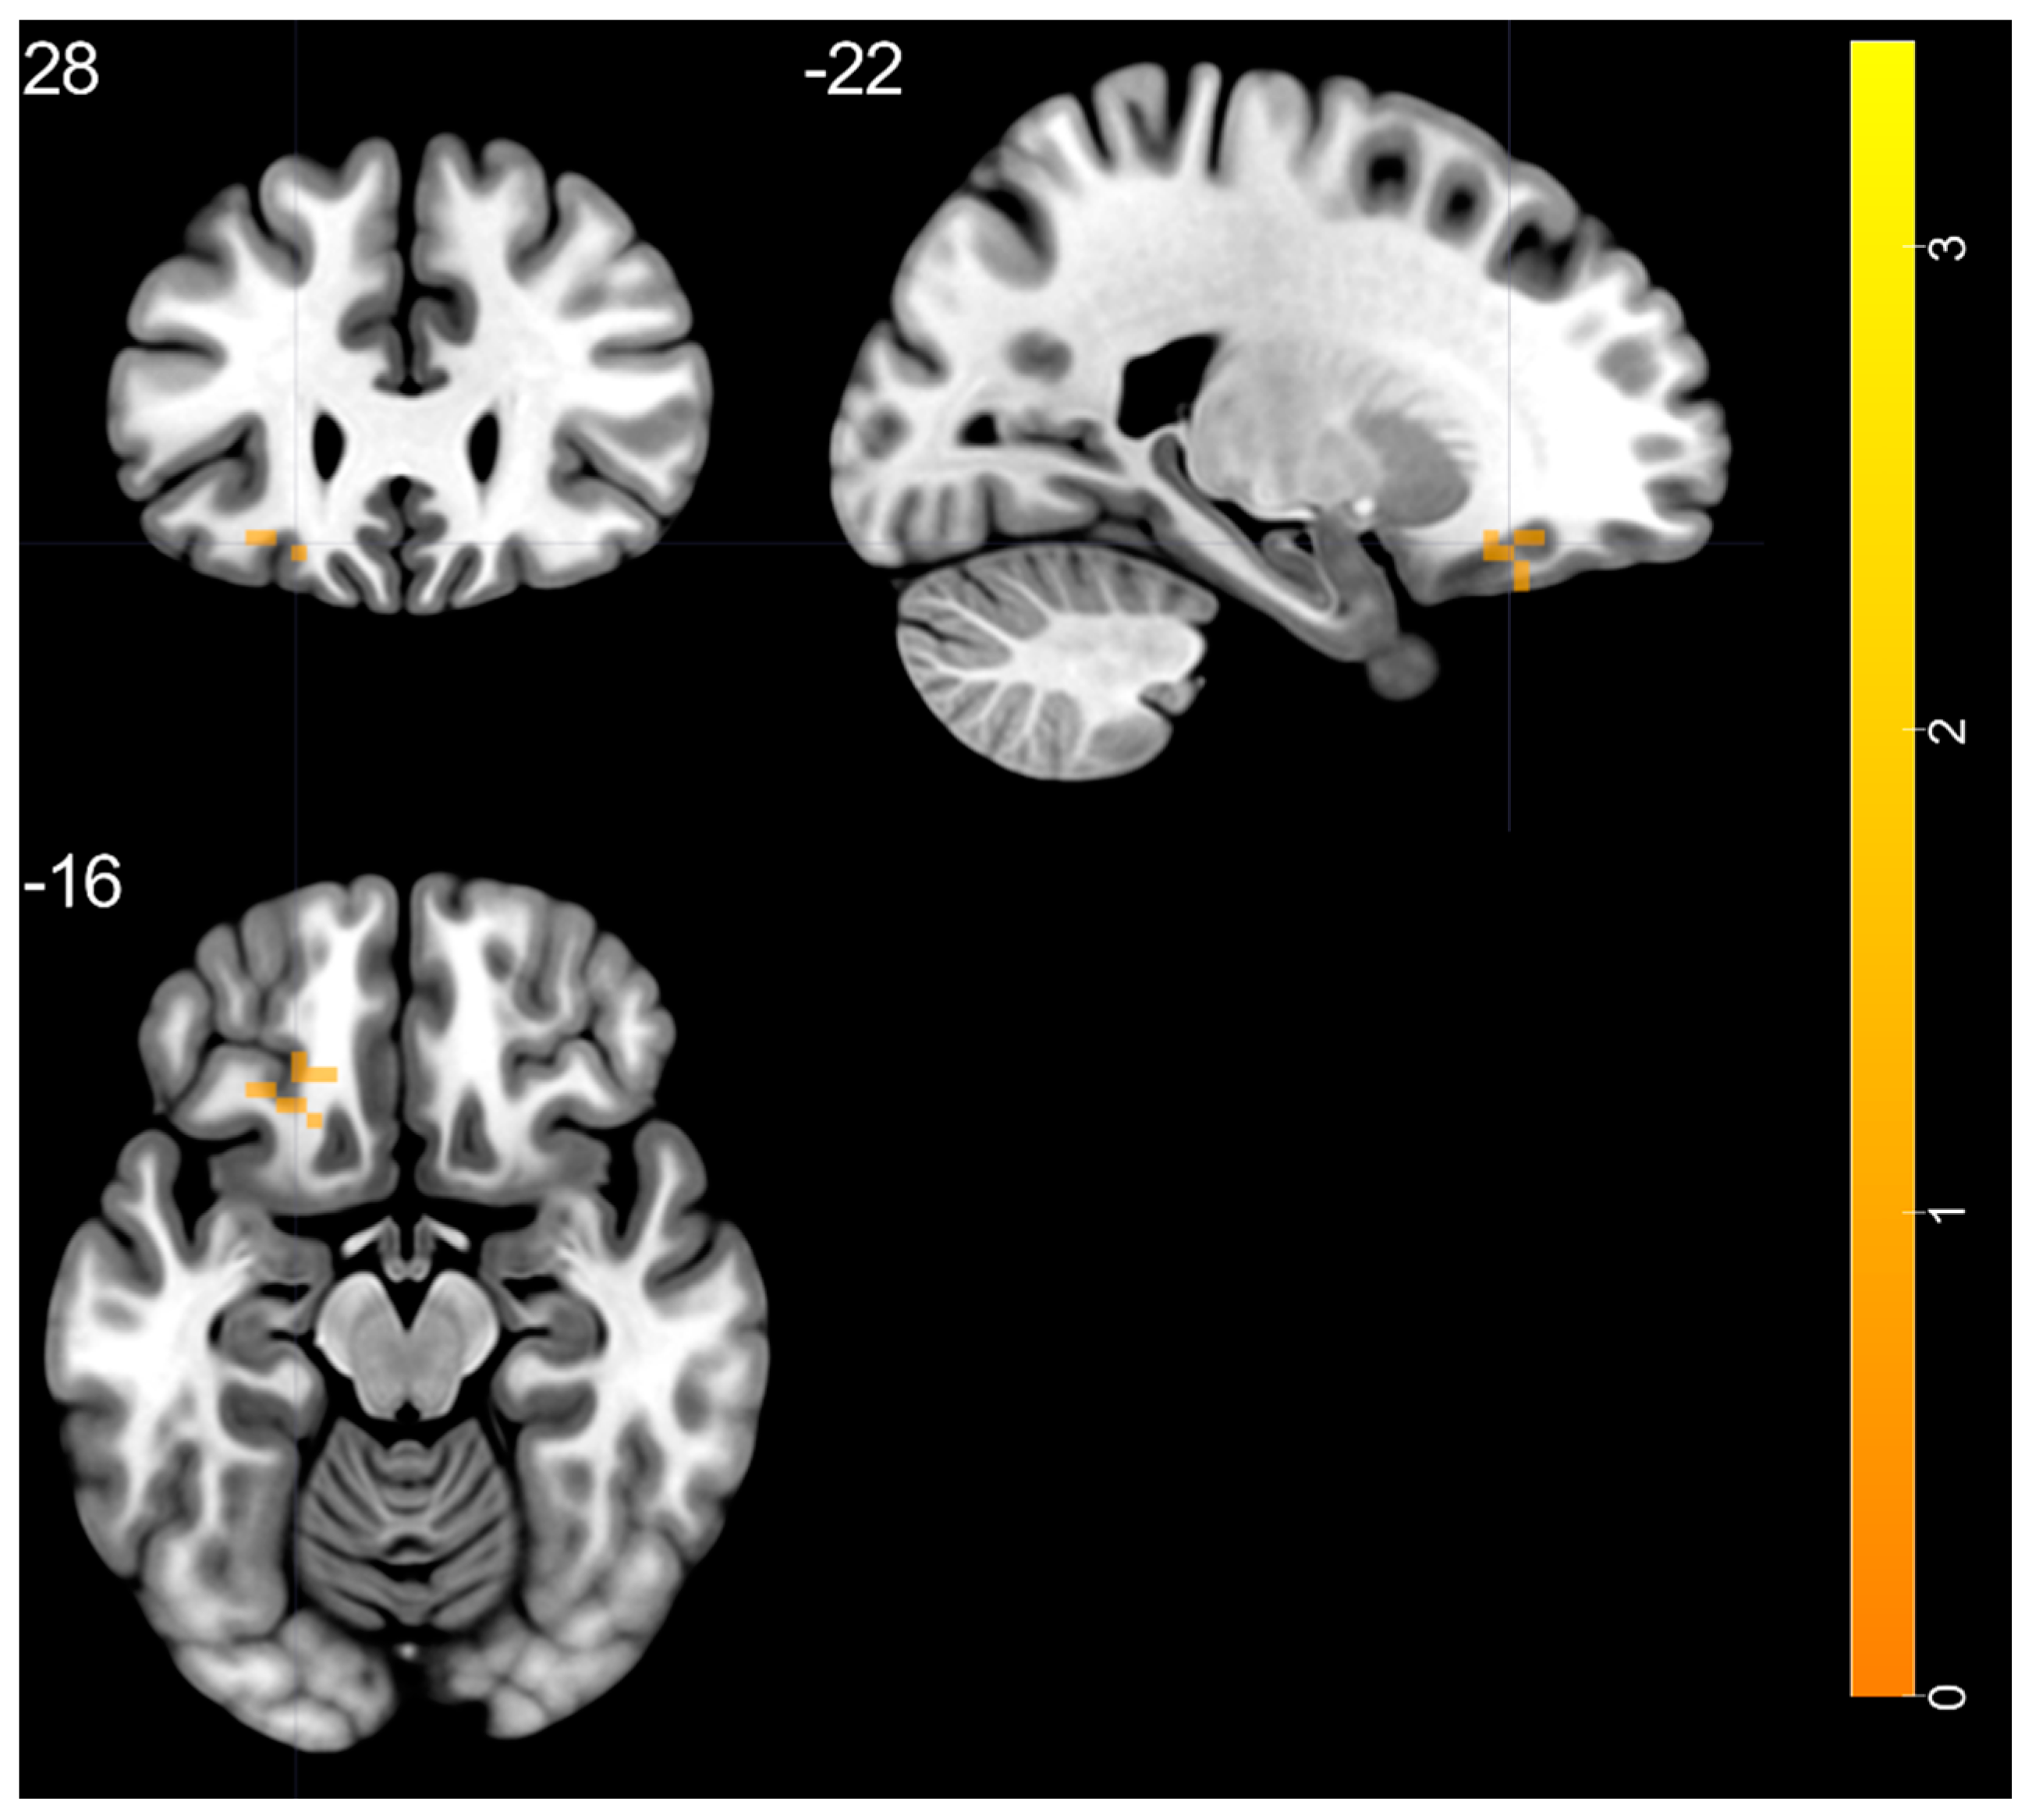

3.5. fALLF: BD vs. HC

| In the slow-5 band | |||||

| BD > HC | |||||

| left MTP—BA 21 | 3.425 | −39 | 15 | −42 | 41 |

| BD < HC | |||||

| None | |||||